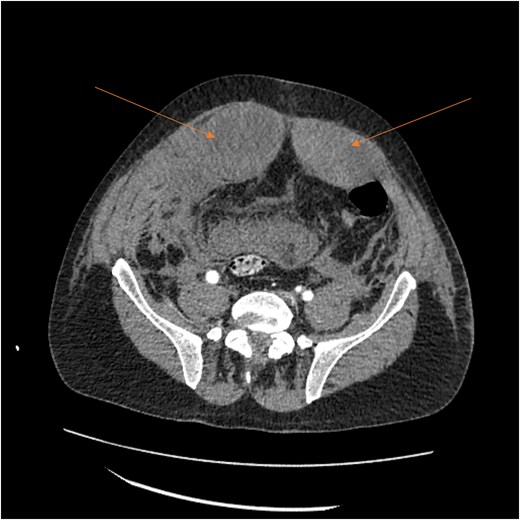

A massive transfusion protocol was initiated, and the patient received four units of packed red blood cells, six units of fresh frozen plasma, two units of platelets, and bicarbonate boluses. A CT abdomen and pelvis was performed to reassess the RSH, revealing an interval enlargement (15.3 × 10.7 × 20.4 cm) with a focal blush at the inferior portion, concerning for active extravasation (Fig. 3). The patient was hemodynamically stabilized and underwent inferior vena cava (IVC) filter placement once his hemoglobin reached 8 g/dl.